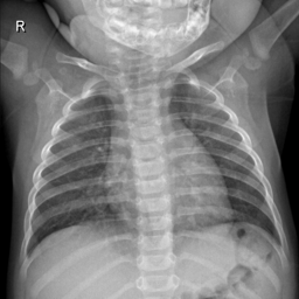

Samples of the dataset are depicted in Figure 3.

Figure 3. An example of an X-ray scan images taken from the dataset (a, b, c) with a label of COVID-19 negative, (d, e, f) COVID-19 positive.